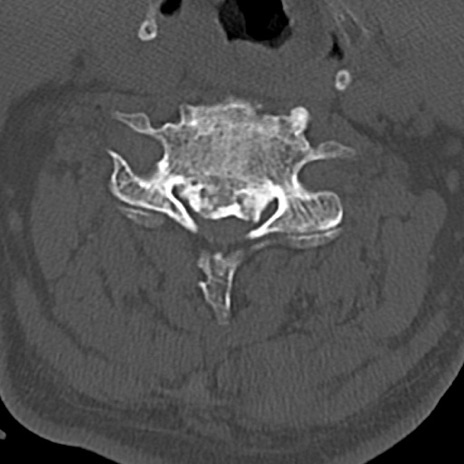

頚椎CT

横断像